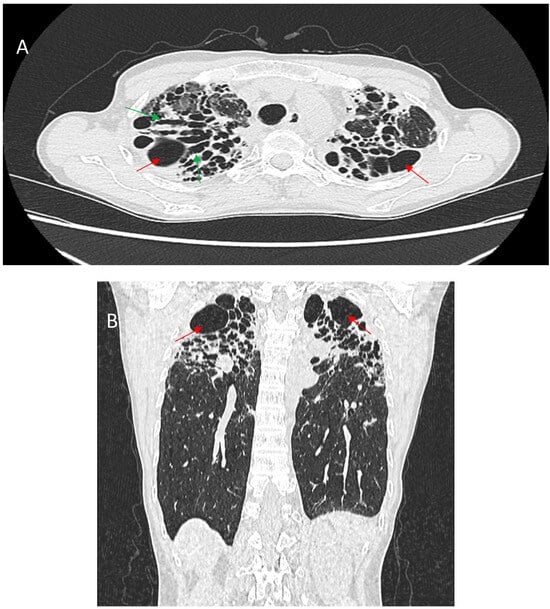

5.1.3. Honeycombing

5.1.5. Bullae and Cysts